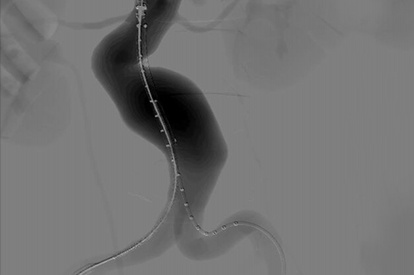

Endovascular Basic Skills Module

SFA Intervention Module

Lower Extremities CTO Module